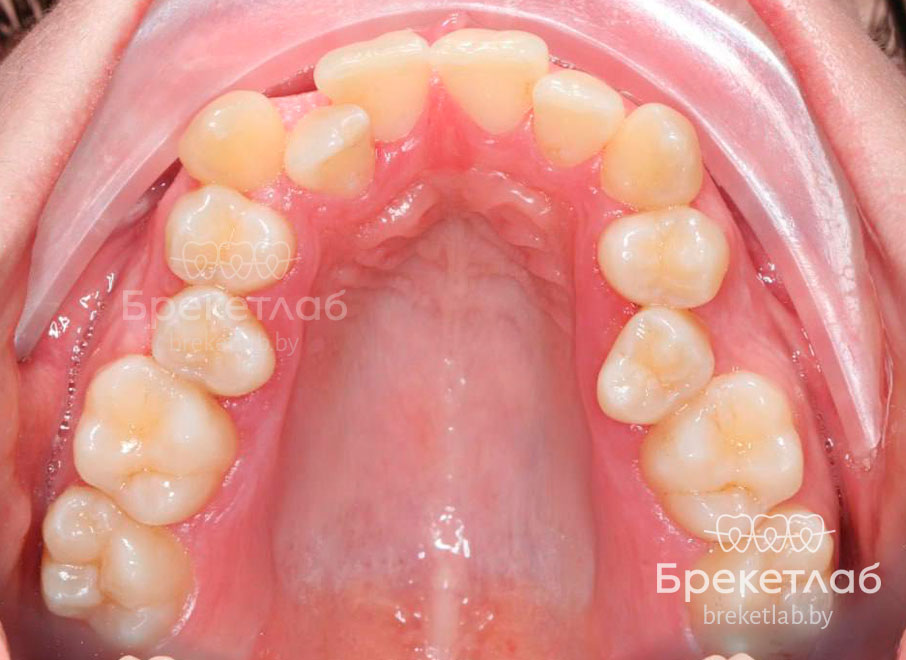

Пациентка обратилась с жалобами на неудовлетворительную эстетику улыбки, вызванную выраженной скученностью передних зубов и полным отсутствием места для бокового резца (зуб 22) на верхней челюсти.

- Деформации зубных рядов: сужение и укорочение дуг, скученность резцов на обеих челюстях.

- Эстетико-функциональные нарушения: смещение центральной линии на 3 мм, ротации зубов и патологическая стираемость зуба 22.